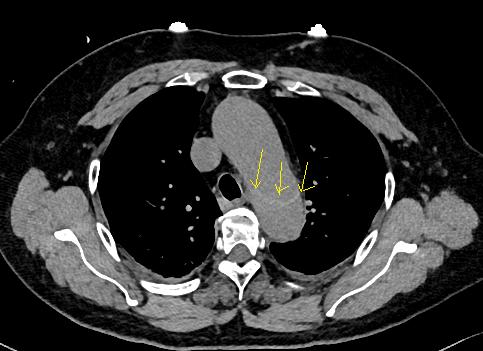

血管内线样阴影,警惕警惕动脉夹层。记住,鲁迅说了,大约肯定有血管内线样阴影,才要怀疑动脉夹层,如果隐隐约约不肯定,不要过度诊断!

下图是:大约肯定有血管内线样阴影!

图25